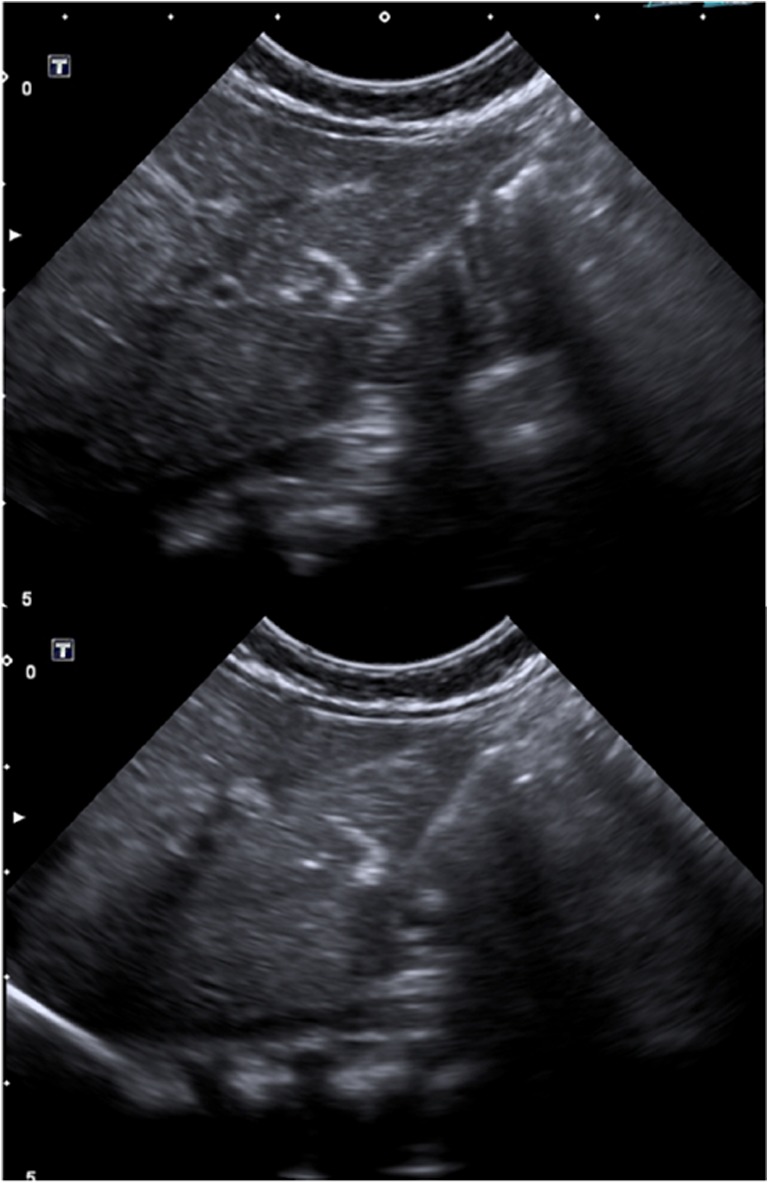

Fig. 3.

Ultrasound-guided percutaneous intrahepatic injection of human liver stem cells (HLSCs) in an infant with neonatal-onset inherited hyperammonemia while in stable metabolic conditions. HLSCs injection and real-time ultrasound images are presented

During the enrolment period, three patients were diagnosed with inherited neonatal-onset hyperammonemia at the study Center. As they met the inclusion criteria, all these three consecutive patients were enrolled into the study and completed the study protocol. Details on patients’ characteristics and HLSC treatment are provided in Table 1. The volumes required for the administration of the scheduled HLSC dosages by ultrasound-guided percutaneous administrations of HLSCs (Fig. 3) ranged from 5 ml to 11 ml per dose. In all patients, each HLSC injection lasted less than 10 min. No injection-related complications were observed. Details of acute safety outcomes after the HLSC administration in the three patients are provided in Table 2. No deaths, adverse events, intrahepatic or extrahepatic complications and no safety issues were registered at long-term follow-up. After HLSCs administration, no signs of infections and no hyperammonemia metabolic decompensations were recorded in any of the three patients. In particular, steadily normal ammonia concentrations were maintained in spite of a ~30% increase in natural protein daily intake (Figs. 4, 5, and 6, panel A and C). Peripheral concentrations of argininosuccinic acid (ASA) in the patient with argininosuccinic aciduria and methylmalonic acid (MMA) in patients with methylmalonic acidemia were stable after HLSCs injections (Figs. 4, 5, and 6, panel B). After this plateau, a progressive increase of ASA and MMA was invariably observed at the longitudinal follow-up (Figs. 4, 5, and 6, panel B). After liver transplantation in patient 1 and 2, ASA and MMA were markedly reduced (Figs. 4, 5, and 6, panel B). Patients 1 and 2 had liver transplantation after 19 and 11 months from HLSCs administration, respectively, with no surgical complications. After transplantation, both patients had immunosuppressive regimen, which included basiliximab preoperatively and on the fourth day and tacrolimus, using therapeutic drug monitoring to reach the standard target range. The post-transplantation course was complicated in patient 1 by two moderate acute rejections 30 days and 9 months after transplantation, as well as the presence of donor-specific antibodies (DSA) against the transplanted liver (anti DQ7 with mean fluorescence intensity of 16,700), but not against HLSCs. After the second episode of rejection, mycophenolate mofetil was added with complete normalization of liver picture. The post-transplant course in patient 2 was complicated by monomorphic Epstein Barr virus infection correlated with post-transplant lymphoproliferative disorder, successfully treated by rituximab. No DSA antibodies were detected in this patient (against either the transplanted liver or the HLSCs). Extensive histopathological analyses of native livers removed at transplantation revealed normal parenchyma and the absence of nodular lesions and it was not possible to identify the exact site of HLSC injection.

Each enrolled, clinically stable patient was scheduled to receive two HLSC intrahepatic injections (once a week for two consecutive weeks). Standard medical treatment was not discontinued. After standardized thawing and washing (see above), resuspended HLSCs in thawing solution at a concentration of 5 × 106 cells/ml were ready for infusion. Two dosage standards were applied according to the patients’ enrolment order. The first patient (patient 1) received 125,000 cells x gram of liver (about 22 × 106 cells) at each administration. Doubled doses were scheduled in patients 2 and 3, both receiving 250,000 cells x gram of liver (about 44 × 106 cells) at each administration. The HLSCs were percutaneously injected into the liver parenchyma under ultrasound guidance and local anaesthesia. All the procedure were performed in the “Regina Margherita” Children Hospital Intensive Care Unit, University Hospital City of Health and Science. Precautionary hospitalization of two weeks after the first HLSCs administration was scheduled for all patients. During and after HLSCs administrations, the patients were monitored continuously for vital signs (temperature, heart and respiratory rates, blood pressure, and oxygen saturation). Liver parenchyma and circulation were monitored by echography and Doppler ultrasound, respectively. No immunosuppression was scheduled during or after HLSCs administrations, according to the evidence of HLSC immunomodulatory activity [15].